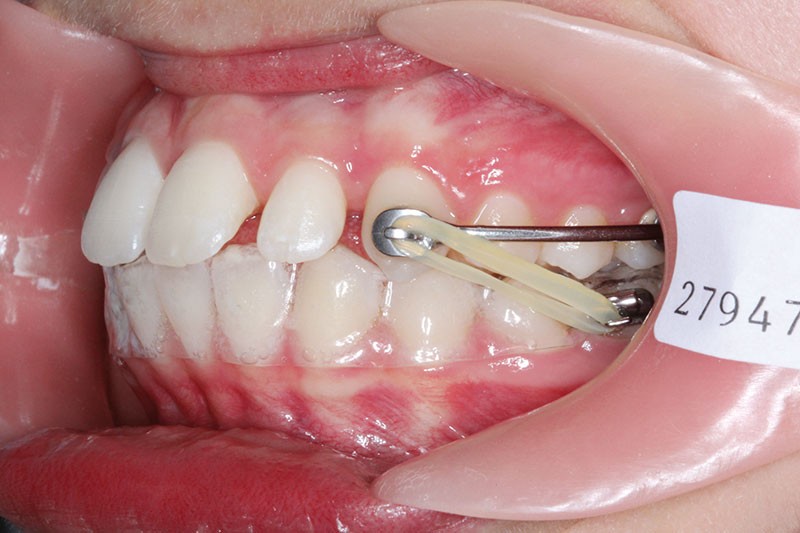

Il a été décidé de mettre en place un système de correction de la classe II “Motion Classe II Carriere” composé de bras latéraux reliant canine et molaire et d’élastiques de classe II ancrés sur des tubes molaires sur 36 et 46 et une gouttière thermoformée portée en permanence. sAprès dérotation des 16 et 26, recul des secteurs latéraux et libération de la croissance mandibulaire nous mettrons en place un système multiattache autoligaturant passif Carriere SLX 022×028 avec la séquence d’arcs suivante :

1re phase : le Motion Appliance Carriere

Afin d’obtenir la correction de la classe II, nous avons fait porter pendant 3 mois une mécanique d’élastiques intermaxillaires, jour et nuit, avec la séquence suivante (fig. 4):

1er mois : élastiques 6oz. ¼”

2e mois et mois suivants : 8 oz. 3/16”